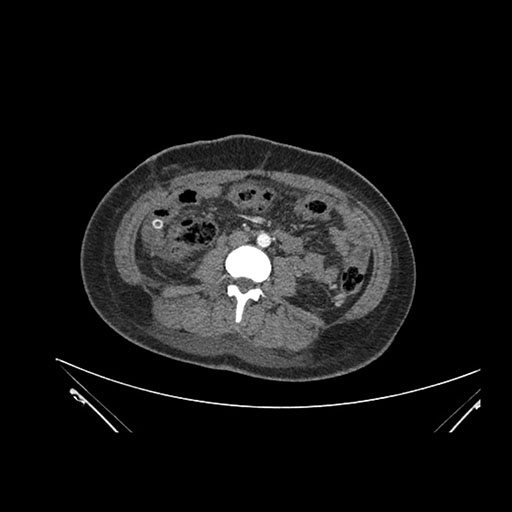

Axial Arterial

Axial Venous